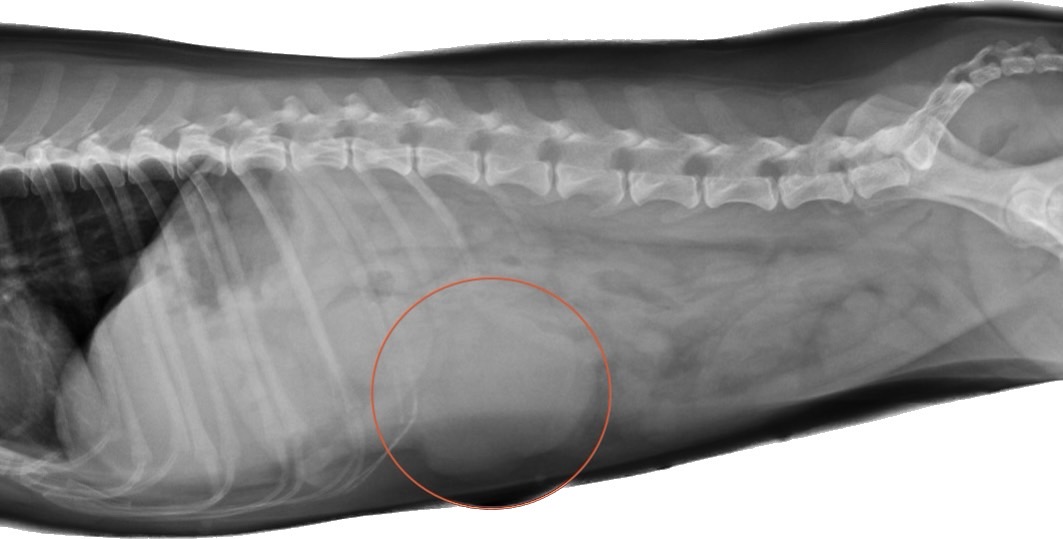

X光檢查結果,阿班的腹腔中長了一顆還不小的團塊,並在超音波下確認是脾臟起源,也同時看到內出血的產生